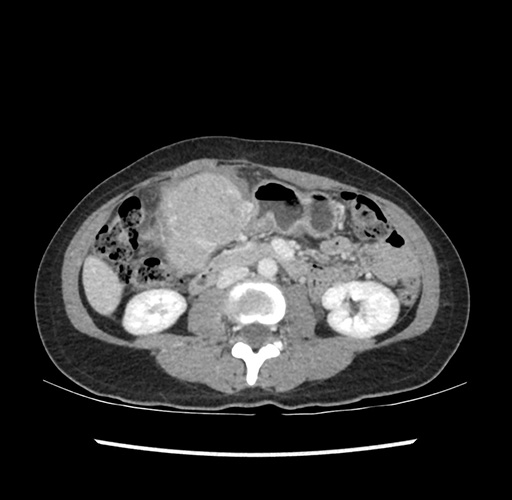

Imaging Analysis

Look through the patient's CT scan to identify any areas of concern for the necessary procedure.

Based on your CT findings, which issue(s) would give reason for "planned slowing down moment(s)" in this case?